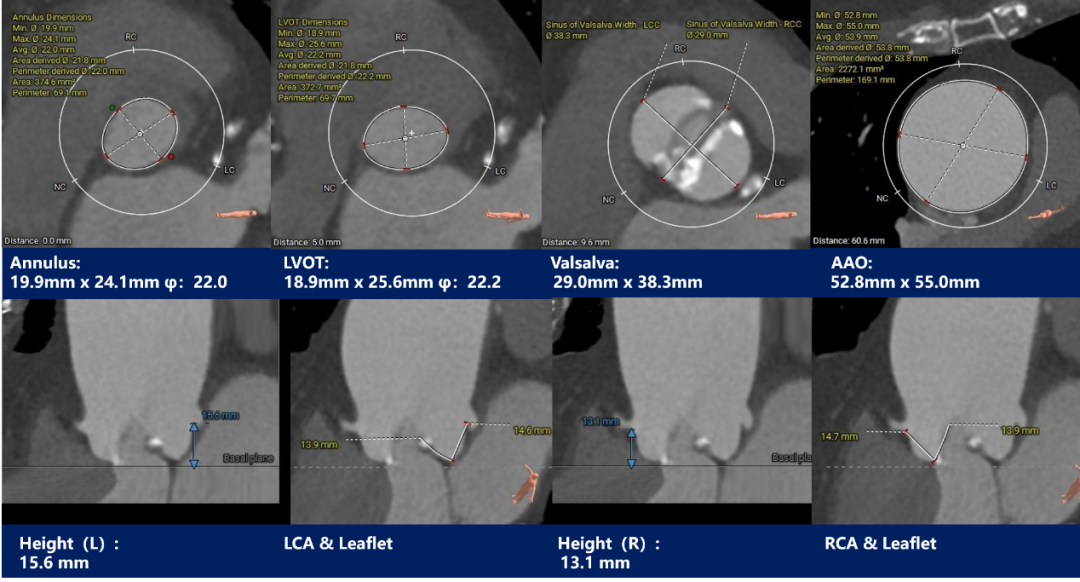

主动脉根部测量

CT特点:Type0型二叶式主动脉瓣,左右冠不同窦;冠脉开口高度可,无冗长瓣叶;横位心,心室壁肥厚。

3. 依据瓣环及瓣上测量结果,行20mm球囊预扩张,预装AV23瓣膜;